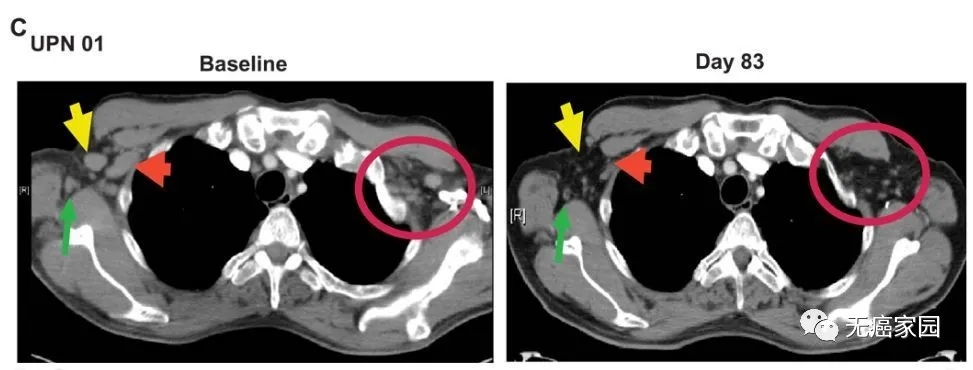

据悉,与Bill一同接受治疗的还有两位白血病患者,三人中,仅在单次治疗后就有两名患者(Bill和Doug)体内的癌细胞被完全清除,呈现完全缓解,另一例为部分缓解。以下是一位患者接受治疗83天后的对比图,可见疗效格外令人惊艳!